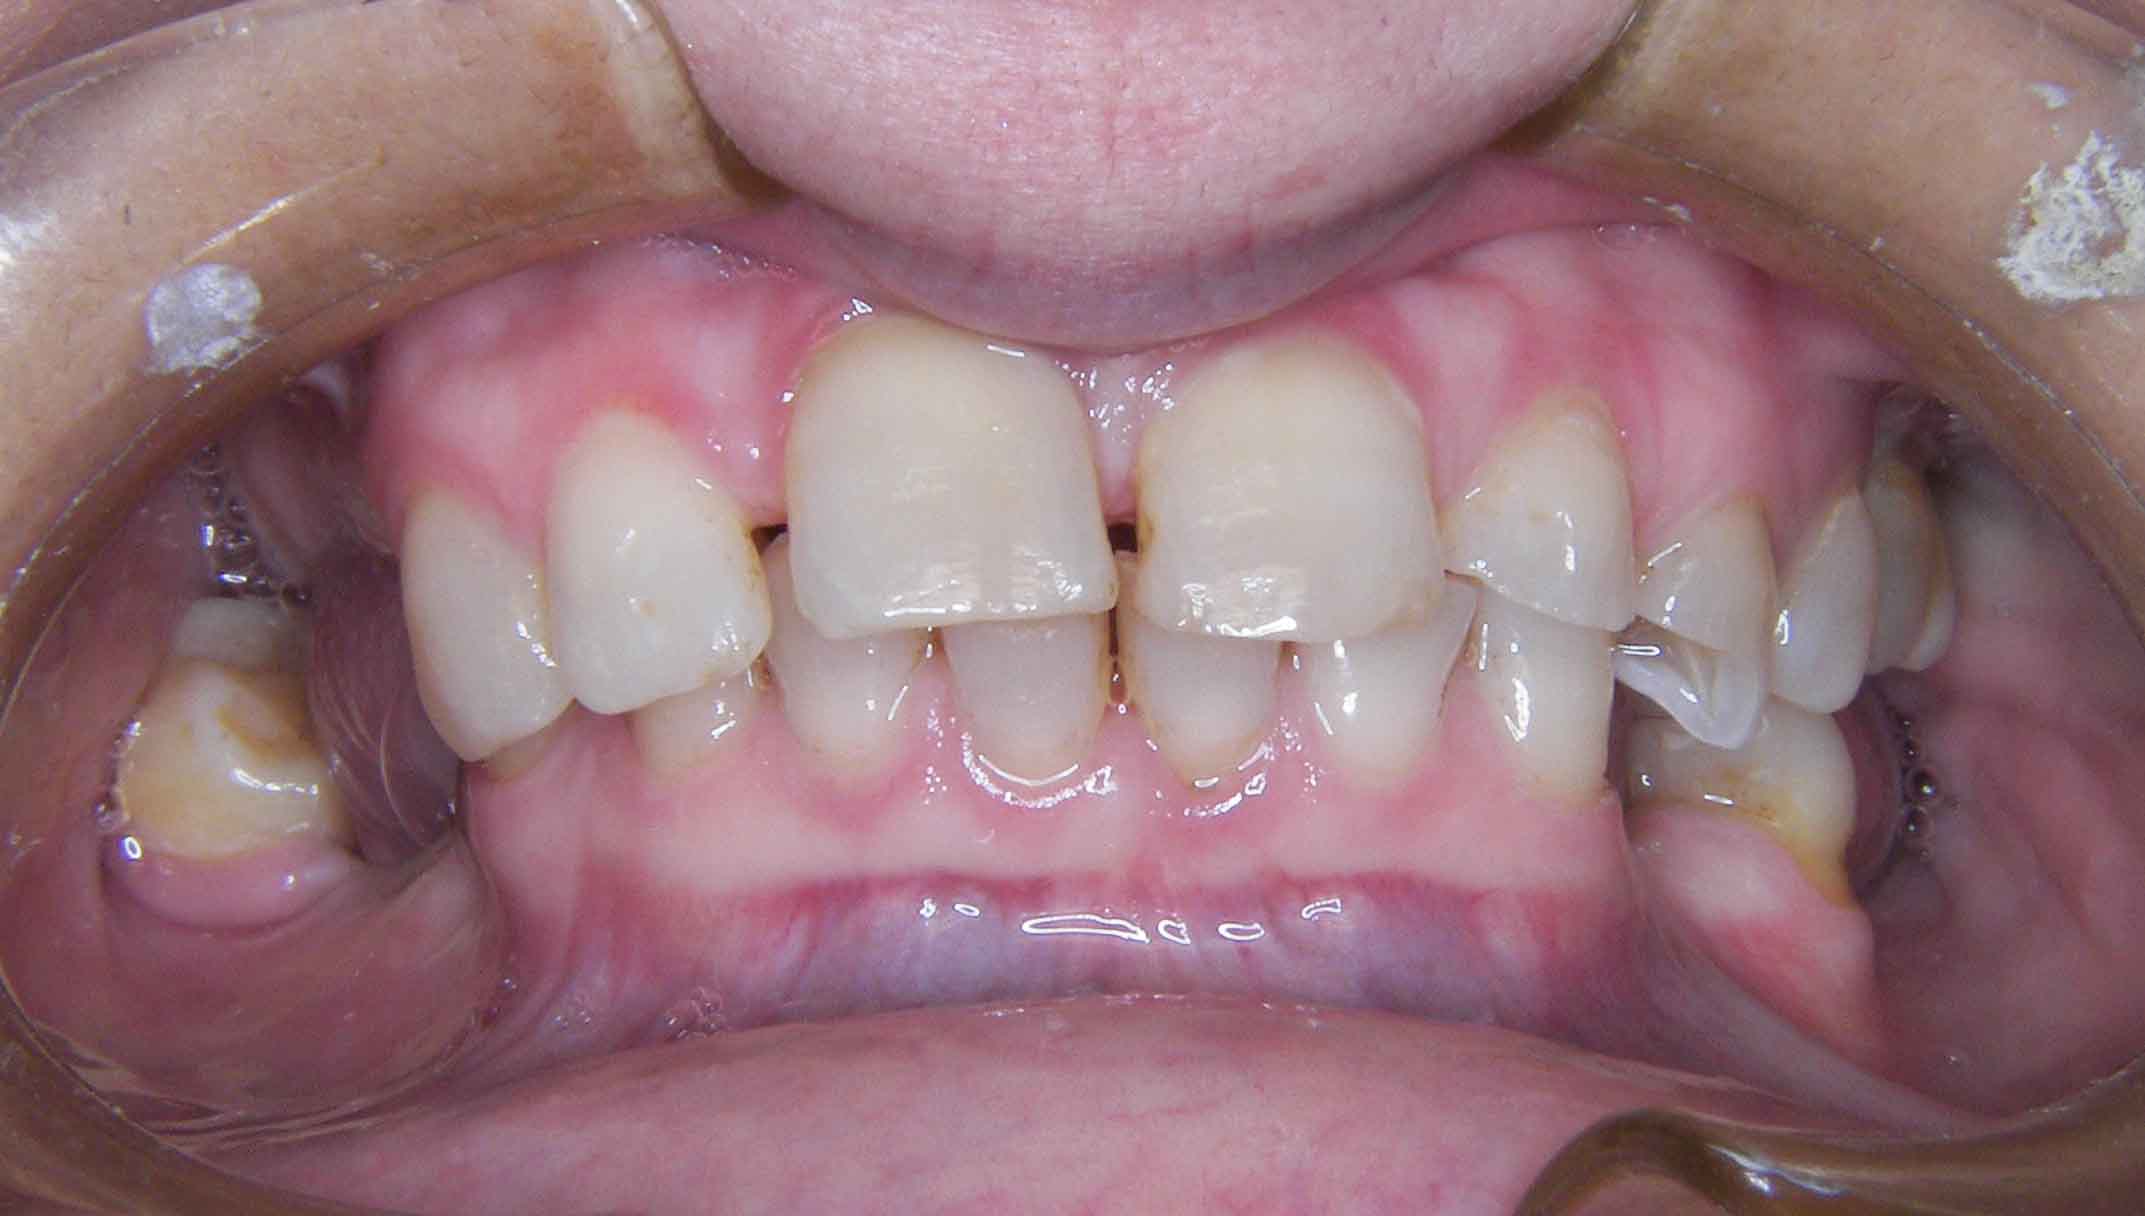

Tooth discoloration caused by tetracyclines

Main problem:

Colour changes due to the use of tetracyclines as a child. Various treatments were done before to try to solve the problem but all of them were unsuccessful.